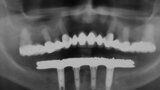

Fig. 5. Prótesis Híbrida inmediata y radiografía control con 6 años post-operatorio

Fig. 6. Prótesis Híbrida inmediata y radiografía control con 6 años post-operatorio